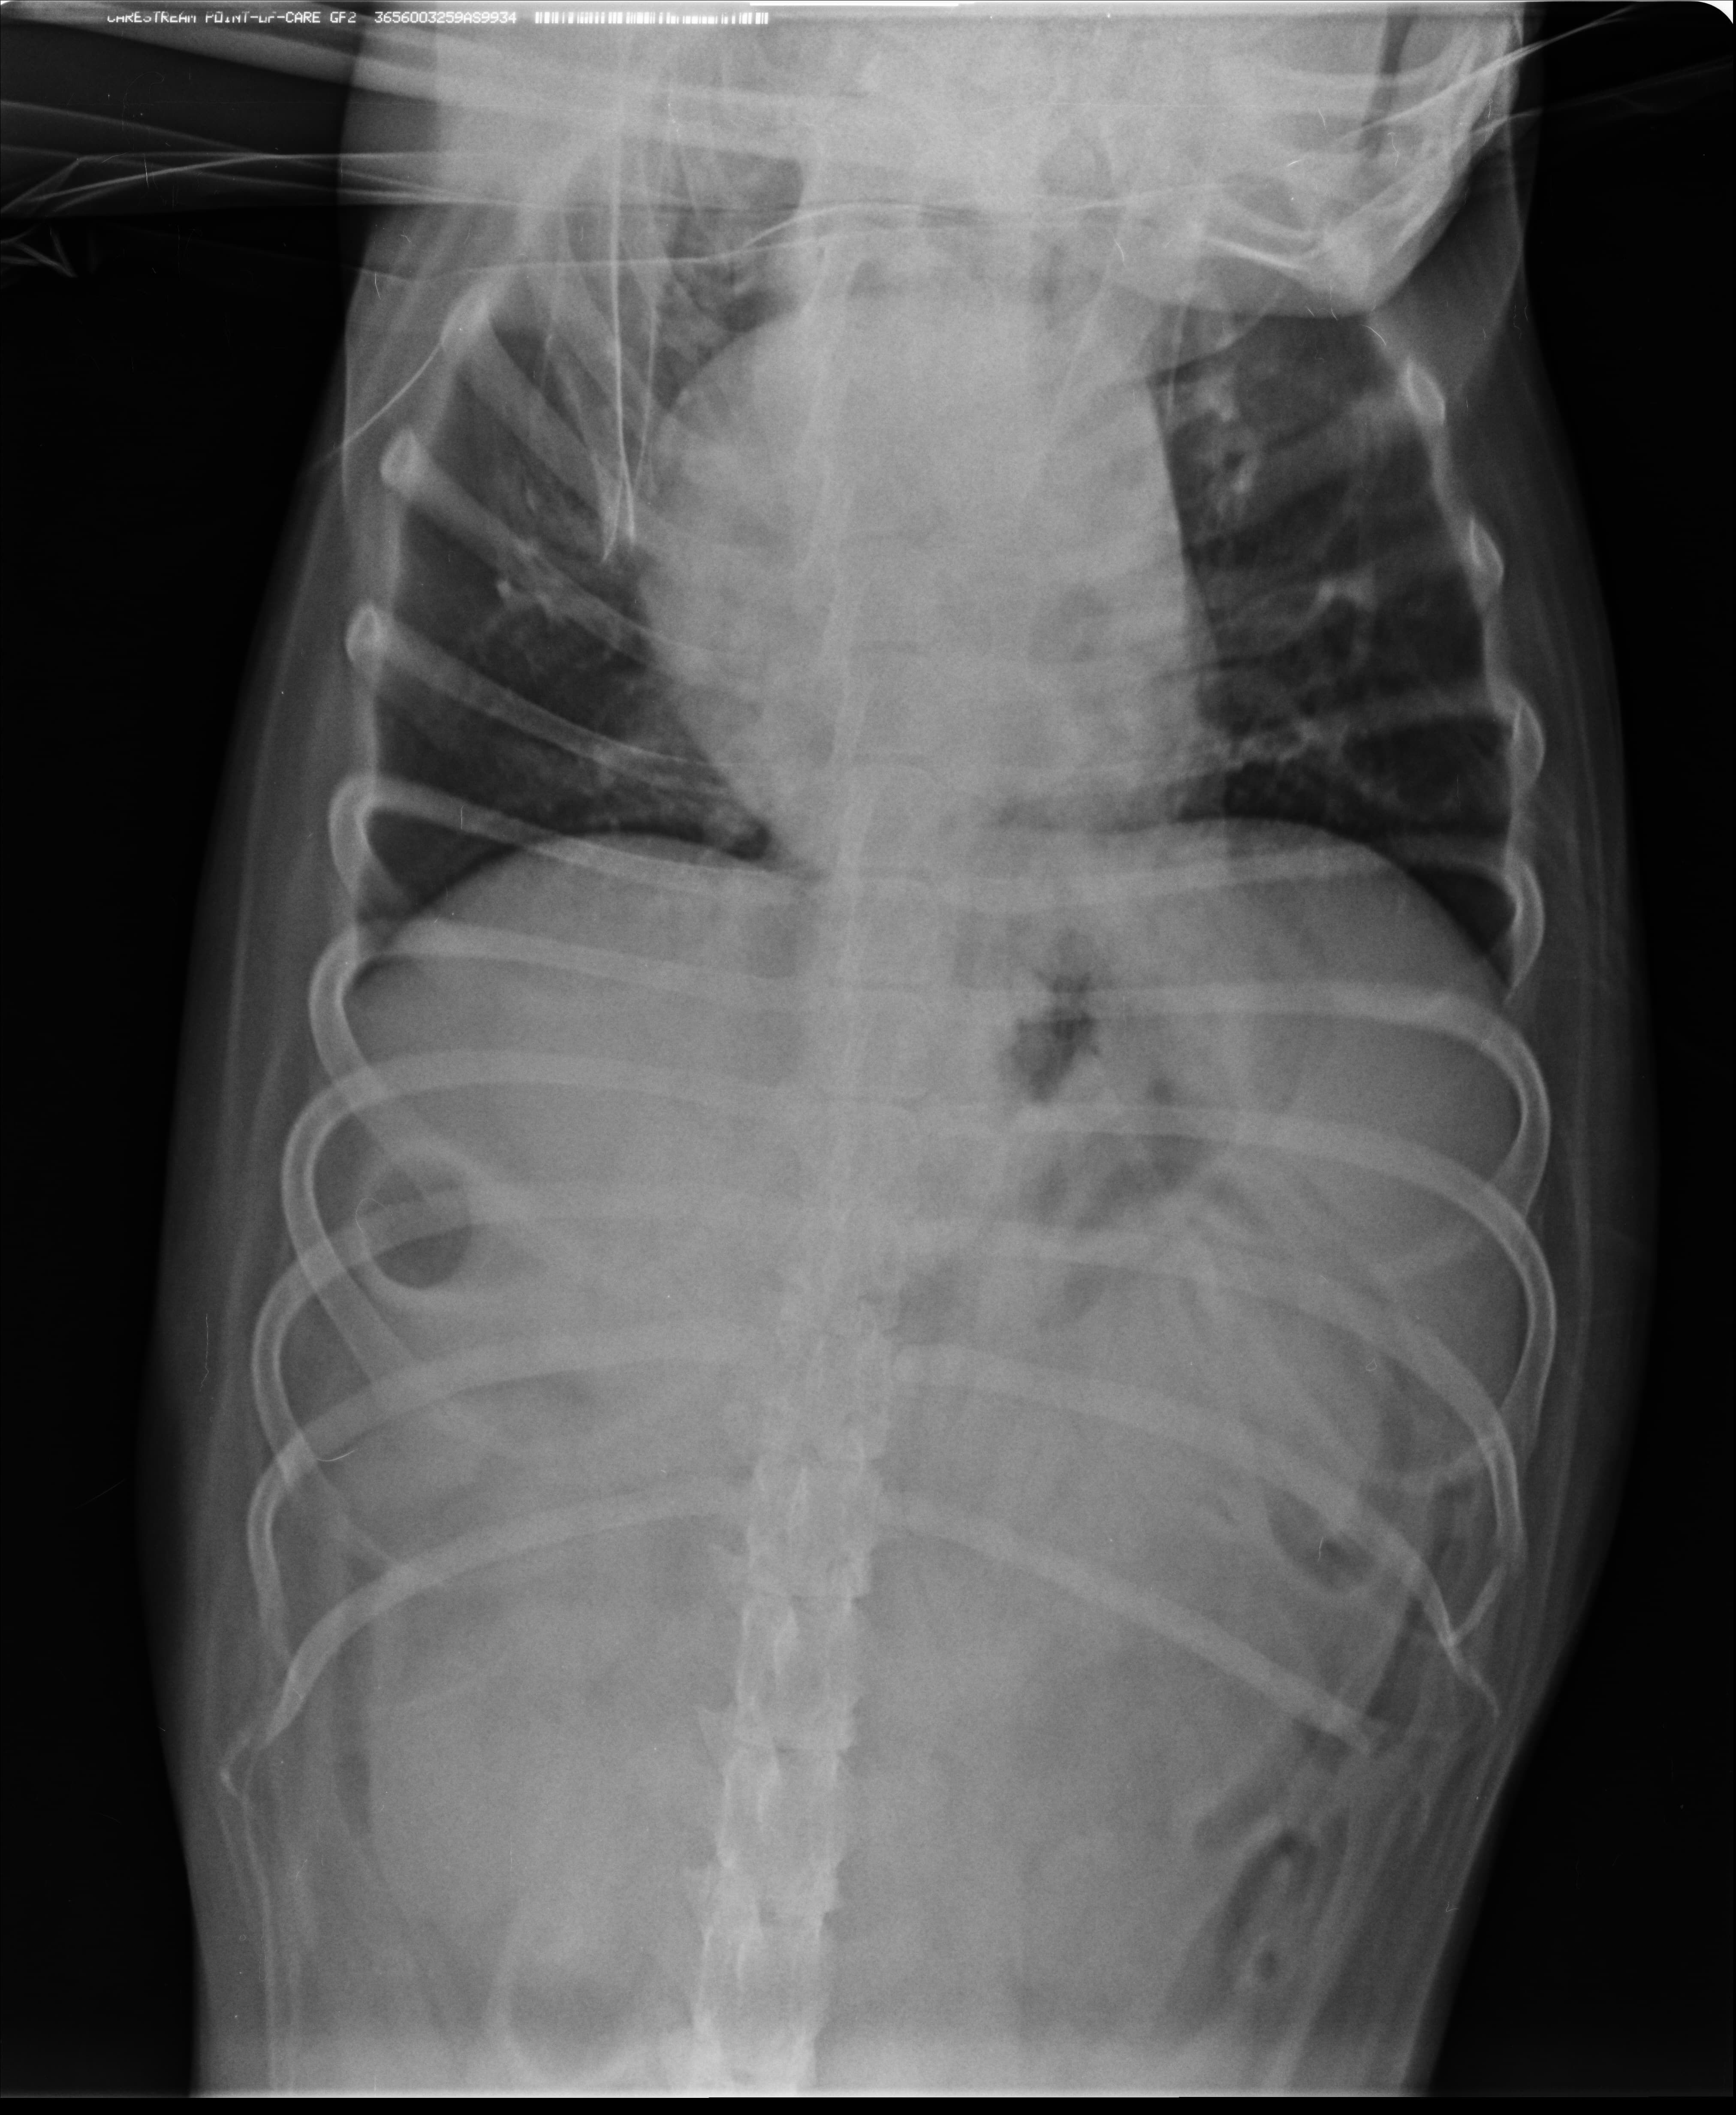

Собака в течение дня регулярно дышит часто (учащенное дыхание), иногда будит нас ночью вот с таким частым дыханием. Кладет на нас лапы, как бы с просьбой ей помочь. В поисках причины этого сделали рентген, оказалось , что у собаки сдавлены, уменьшены в размерах легкие.

История выявления приступов такая: собака была бездомной, ее отвезли на стерилизацию и в процессе операции выявилось, что у собаки диафрагмальная грыжа. Во время операции останавливалось дыхание (если я правильно поняла/если такое бывает), собаке делали искусственную вентиляцию легких. Видимо в результате травмы и операции органы брюшной полости подали вперед и "сдавили" легкие. Возможно, что-то некорректно пишу.

Т.е., видимо была травма, которая повлекла грыжу. Была операция. И имеем легкие меньшего размера, чем у здоровой собаки.

Прилагаю заключение врача по УЗИ сердца ; рентген грудной клетки; биохимический анализ крови от июля 2018г.